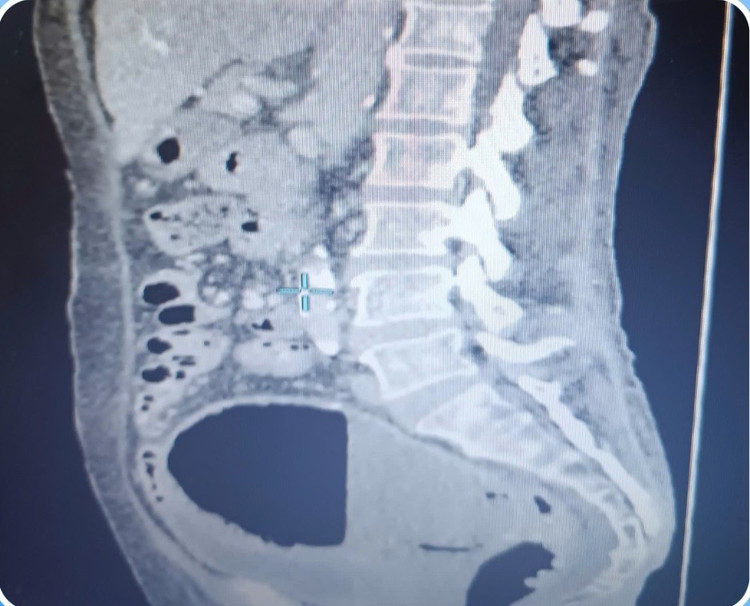

BSCKI. Đỗ Hoàng Sanh, Khoa Sản Phụ Khoa Bệnh viện Đa khoa Xuyên Á cho biết: “Trong quá trình phẫu thuật, chúng tôi nhận thấy tử cung to gần 12x12cm, chạm mềm nhũn, thành cơ tử cung mỏng chứa đầy dịch bên trong, may mắn dịch mủ chưa chảy ra hai tai vòi tử cung vào ổ bụng.

Ê-kíp đã tiến hành gỡ dính ruột và cắt trọn vẹn tử cung với hai phần phụ. Tử cung sau khi cắt ra thấy bên trong chứa đầy dịch mủ hôi, màu trắng đục, đã được lấy dịch cấy vi khuẩn làm kháng sinh đồ để hỗ trợ điều trị hậu phẫu”.

uo-mu1-4234.jpg

Cắt trọn vẹn tử cung với hai phần phụ - Ảnh BVCC